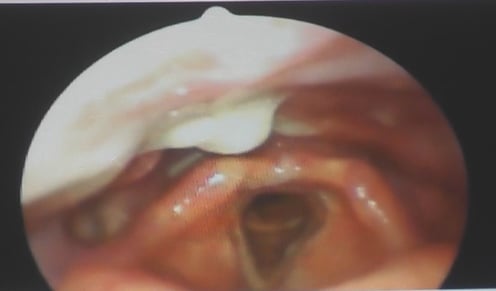

内視鏡で喉から気管の入り口を覗いた写真です。

鼻から鼻水が喉の背中側を伝わって垂れてきたところで、真ん中の暗いところが気管です。ここに唾液や食べ物が入る事を誤嚥と言います。

鼻水が今にもぽたっと落ちそうです。

落ちた先は、気管です。